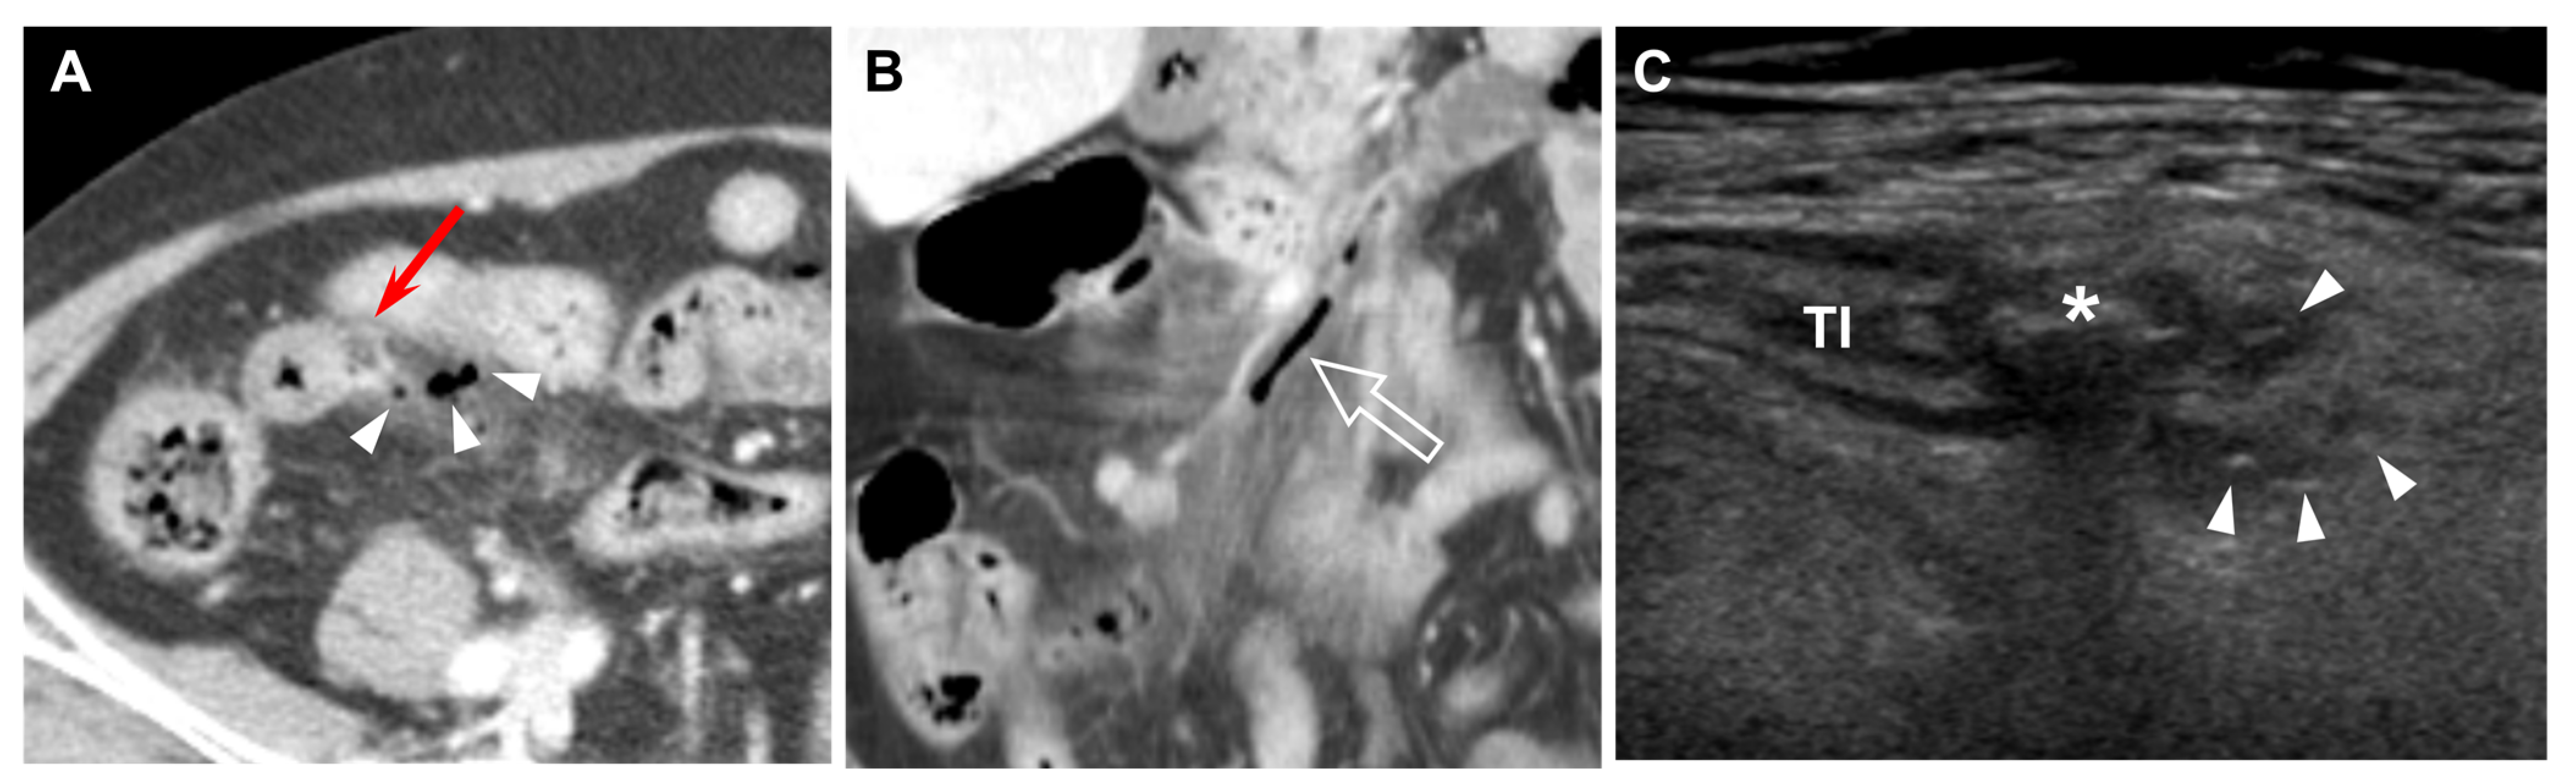

Figure 4. Sixty-three-year-old female (patient #9) with acute perforated ileal diverticulitis. (A,B) Axial and coronal reformatted CT scans show inflamed diverticulum (red arrow), with extraluminal gas (arrowheads) representing perforation. Mesenteric fat infiltration, terminal ileal wall thickening, and mesenteric venous gas (open arrow) are also seen. (C) US scan demonstrates an outpouching inflamed diverticulum with central hyperechoic fecalith (*) connecting to terminal ileum (TI), and tiny hyperechoic reverberating dots (arrowheads) represent extraluminal air bubbles.

The CT findings for acute ileal diverticulitis are summarized in Table 2. All 17 patients had ileal diverticulum along the mesenteric border. Inflamed diverticulum was seen in 16 patients (94.1%) (Figure 1). The remaining patient did not have an inflamed diverticulum at the center of ileal wall thickening with abscess; however, adjacent ileal diverticula supported the diagnosis of acute ileal diverticulitis with perforation, and barium study after 1 month demonstrated two ileal diverticula along the mesenteric border (Figure 2). Three patients had radiodense fecalith within the inflamed diverticulum (Figure 3). All 17 patients had mesenteric fat infiltration with varying degrees and ileal wall thickening. Five patients (29.4%) were diagnosed with perforated ileal diverticulitis, which had the following findings: abscess (n = 2) (Figure 2), extraluminal fluid with air (n = 3) (Figure 4), and/or focal defect in the diverticular sac (n = 2) (Figure 5). Mesenteric venous gas (Figure 4) and mesenteric venous thrombosis were seen in two patients (11.8%), respectively.

The US findings for acute ileal diverticulitis are summarized in Table 3. All patients showed outpouching inflamed diverticular sac connecting to the ileum, peridiverticular inflamed fat presenting as hyperechoic fat around the diverticulum, and increased color flow to the diverticulum and surrounding inflamed fat on CDI (Figure 1). The inflamed diverticulum exhibited variable echogenicity (Figure 2 and Figure 3). Like CT findings, eight patients had a single diverticulum and nine patients had multiple diverticula. Unlike CT, US examinations diagnosed perforated ileal diverticulitis in seven patients. The findings indicated that five patients had both abscess and extraluminal air bubble (Figure 4 and Figure 5), one patient had only extraluminal air bubble (Figure 6), and one patient had only abscess.